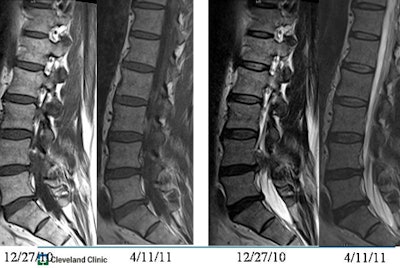

In their own study, Cleveland Clinic researchers followed for two years 246 patients who had a variety of functional pain issues. Sixty-four percent of those with back and leg pain had a herniation on imaging, and 57% of those with back pain had a herniation.

However, over six weeks there was complete resolution in 23% of those with herniation. Also, 13% of those with herniation developed a second herniation between the first and second studies (Radiology, November 2005, Vol. 237:2, pp. 597-604).

"There is no correlation between the number of herniations and how big they were and the patient's symptoms, and whether they were herniated didn't seem to correlate with how the patient did," Modic said.